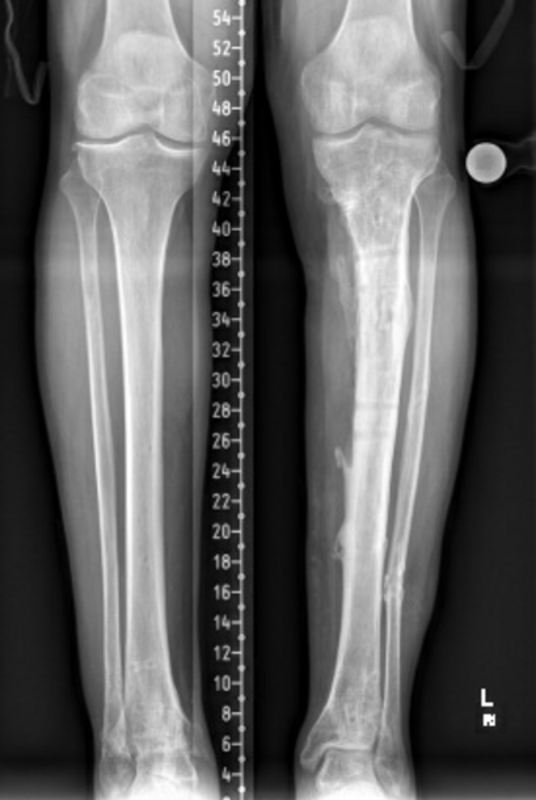

Kurze Vorgeschichte: Herr S, ein 67-jähriger Patient, erhielt 2011 (Abbildung 1) bei ausgeprägter Gonarthrose eine primäre KTEP rechtsseitig. Im weiteren Verlauf zog er sich 2017 eine periprothetische Tibiafraktur zu, die mit einem Knieendoprothesenwechsel auf ein achsgeführtes Implantat (Abbildung 2) und Schaftverlängerung der Tibia im September 2017 ex domo therapiert wurde. Im Verlauf zeigten sich eine anhaltende Sekretion und eine partielle Nekrose am unteren Wundpol.

Im weiteren Verlauf zeigten sich die Weichteile des rechten Unterschenkels zunehmend mazeriert und belegt. Zudem sei der Patient erneut gestürzt. Eine erneut durchgeführte Röntgendiagnostik zeigte erneut eine periprothetische Tibiafraktur (Abbildung 3) bei einliegender achsgeführter KTP mit langem tibialem Stem und bekanntem periprothetischem Infekt mit Candida parapsilosis. Wir haben die Befunde ausführlich mit dem Patienten besprochen und in Zusammenschau der Befunde schließlich die Indikation zur Oberschenkelamputation gestellt.

Diese konnte komplikationslos im Mai 2018 durchgeführt werden (Abbildung 4 und 5).